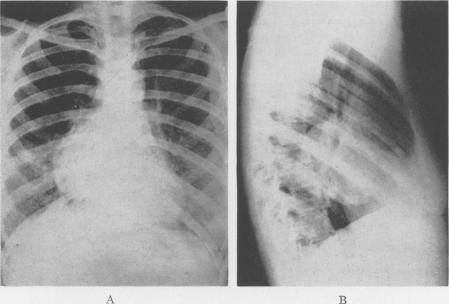

Bronchiogenic Cysts of the Mediastinum.

Ann Surg. 1948 Mar;127(3):476-502. doi: 10.1097/00000658-194803000-00010.